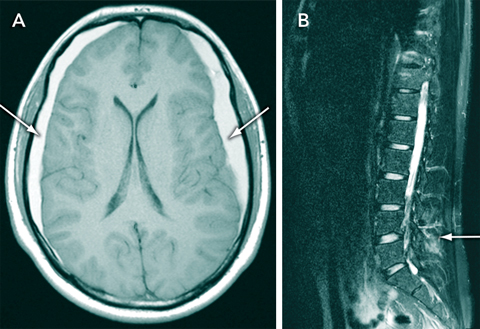

A 16-year-old boy with a 3-month history of intermittent postural headaches presented with sudden worsening headache after a game of soccer. The results of a neurological examination were unremarkable. Magnetic resonance imaging showed elongation of the midbrain, bilateral frontoparietal subdural haematomas (Figure, A), and a collection of fluid within the soft tissues overlying the lumbar spine (Figure, B). The cerebrospinal fluid (CSF) opening pressure on lumbar puncture was low (60 mmHg). Spontaneous intracranial hypotension was diagnosed, and the response to conservative treatment was good.

Intracranial hypotension has characteristic imaging features, which include elongation of the midbrain, linear enhancement of the pachymeninges and subdural effusions.2 Patients are predisposed to subdural haemorrhage after minor trauma as a result of “stretching” of the dural veins. Intracranial hypotension is commonly misdiagnosed as migraine, meningitis or a psychogenic disorder.1 Most cases resolve spontaneously, but intractable headaches may be successfully treated with steroids, epidural blood patches or surgery.1